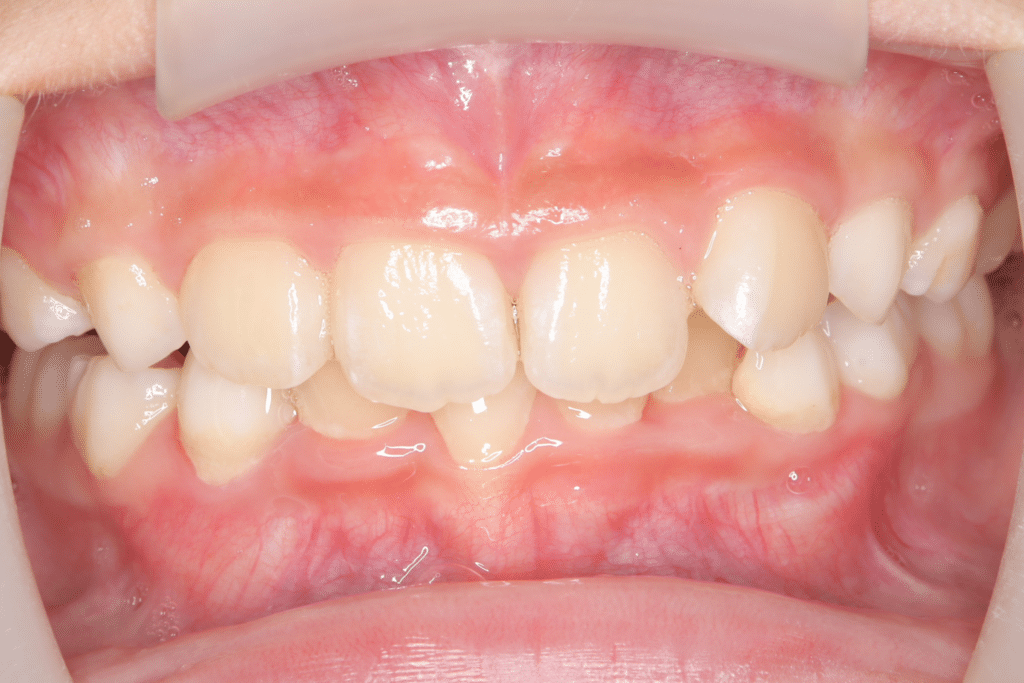

過蓋咬合(かがいこうごう)を改善

【まとめ】

症状:過蓋咬合(かがいこうごう)

期間:8か月

開始年齢:(9歳2ヶ月)~

終了年齢:(9歳10ヶ月)(過蓋咬合は改善したが、叢生がまだ残っているため、今後は叢生の治療を開始予定)

費用の概算:70〜100万